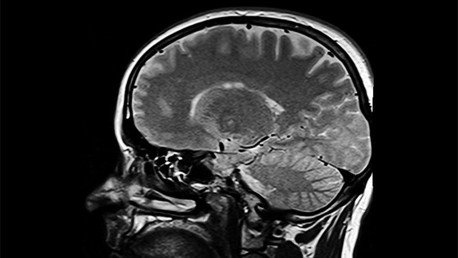

El equipo de cirujanos encabezado por Hrayr Shahinian del Skukkbase Institute de Los Ángeles descubrió que el supuesto tumor de la mujer era, en realidad, el embrión de su gemelo, que nunca llegó a desarrollarse, aunque presentaba huesos, pelo y dientes.

El médico explicó a la NBC de Los Angeles que los tumores de este tipo, conocidos como teratoma, son muy escasos. "Este es mi segundo caso, y eso que probablemente habré extirpado entre 7.000 u 8.000 tumores cerebrales", explicó.